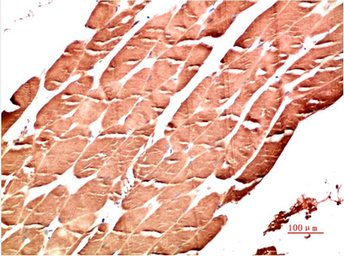

IHC-P analysis of human skeletal muscle tissue using GTX34142 AMPK alpha 1 antibody [9G3].

Dilution : 1:200